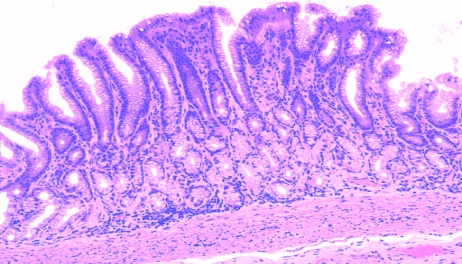

23 Пилорический отдел желудка: Полый оболочечный слоистый орган. Рельеф – складки, желудочные ямочки(глубокие). Стенка оболочки: слизистая (эпителий – однослойный призматический железистый, собственная пластинка – РВСТ, пилорические железы желудка, мышечная пластинка – гладкая мышечная ткань 3 слоя циркулярный, продольный, циркулярный), подслизистая – РВСТ,сосуды, мышечная – 3 слоя гладкой мышечной ткани наружный продольный, средний циркулярный, внутренний – косой, серозная – РВСТ, мезотелий. В составе собственных железы различают 5 типов клеток: малодифференцированные клетки (шейка), шеечные мукоциты, главные экзокриноциты (дно), париентальные клетки (тело, шейка) эндокринные (главные) клетки (дно).

6 Дно желудка: 1- слиз. обл.2-подслиз. обл.3 – мыш. обл.4 – сер. обл.5 – эпителий.6 – соб-я пластинка слиз. обл.7 – мыш. плст слиз. обл. Полый оболочечный слоистыйВорган.Оболочки: слизистая (эпителий – однослойный призматический железистый, собственная пластинка – РВСТ, пилорические железы желудка, мышечная пластинка – гладкая мышечная ткань 3 слоя циркулярный, продольный, циркулярный), подслизистая – РВСТ,сосуды, мышечная – 3 слоя гладкой мышечной ткани наружный продольный, средний циркулярный, внутренний – косой, серозная – РВСТ, мезотелий.